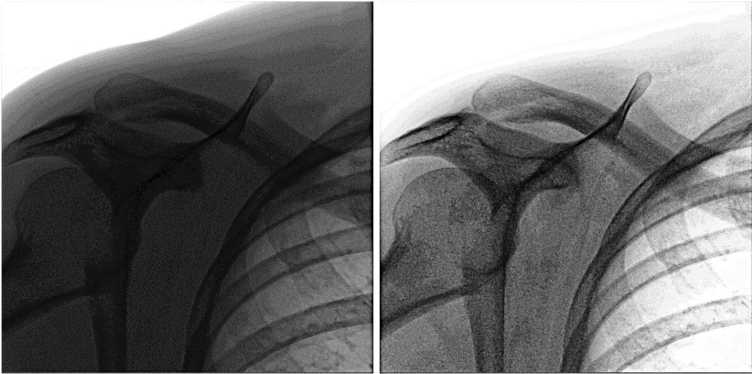

На рис. 4 можно видеть результат применения данного LUT. Можно заметить, что в результате такого преобразования существенно увеличивается «читаемость» костей.

Рис. 4. Слева – исходное изображение, справа – результат применения LUT для плотных тканей

Fig. 4. Left – original image, right – result of applying LUT for dense tissues